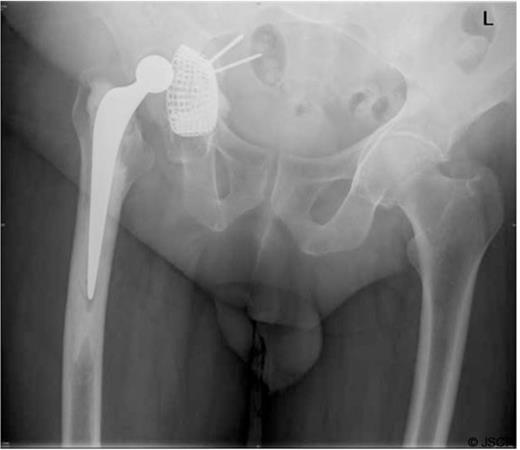

The acetabular screws were seen projecting medially into the pelvis with the anterior screw closely abutting the external iliac artery and vein causing compression (Figure 2).

A CT Scan of the pelvis showing compression of external iliac vein by acetabular screw